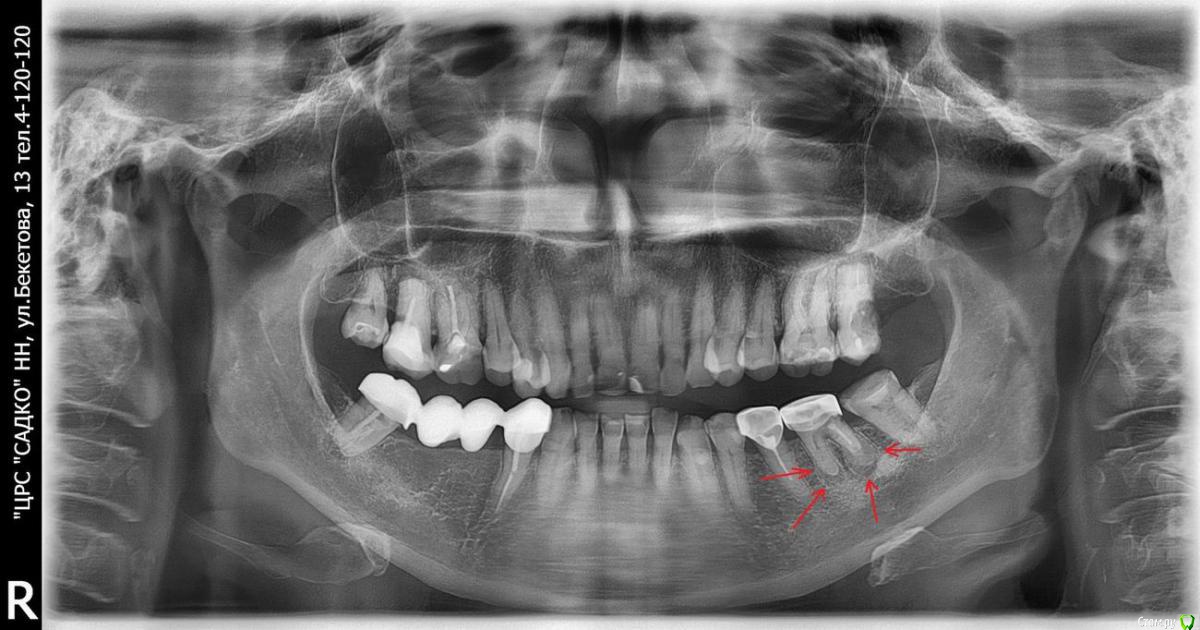

usilitel Опубликовано 10 марта, 2019 Поделиться Опубликовано 10 марта, 2019 На снимке видно что вокруг корней зуба что-то явно ненормальное образовалось (возможно киста?).При этом сам зуб не беспокоит.Были у двух разных врачей - сказали что раз не беспокоит - то ничего делать не надо.А ваше мнение? Ссылка на комментарий

red_butler Опубликовано 10 марта, 2019 Поделиться Опубликовано 10 марта, 2019 требуется повторное лечение корневых каналов 2 Ссылка на комментарий